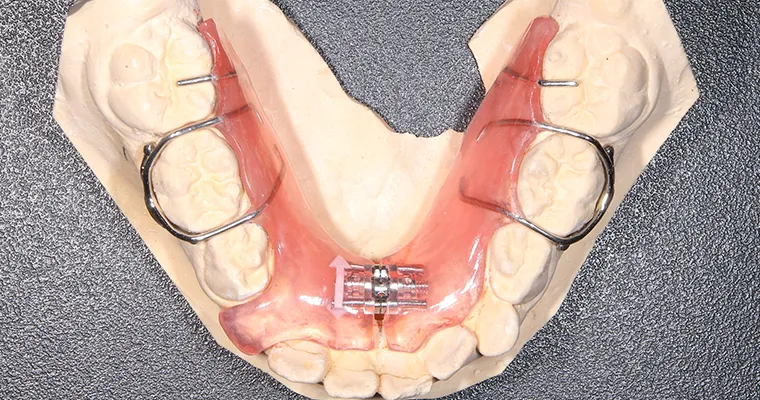

使用矯正装置 上

使用矯正装置 下

| 治療内容 | 拡大床矯正 EF Lineで筋機能療法 |